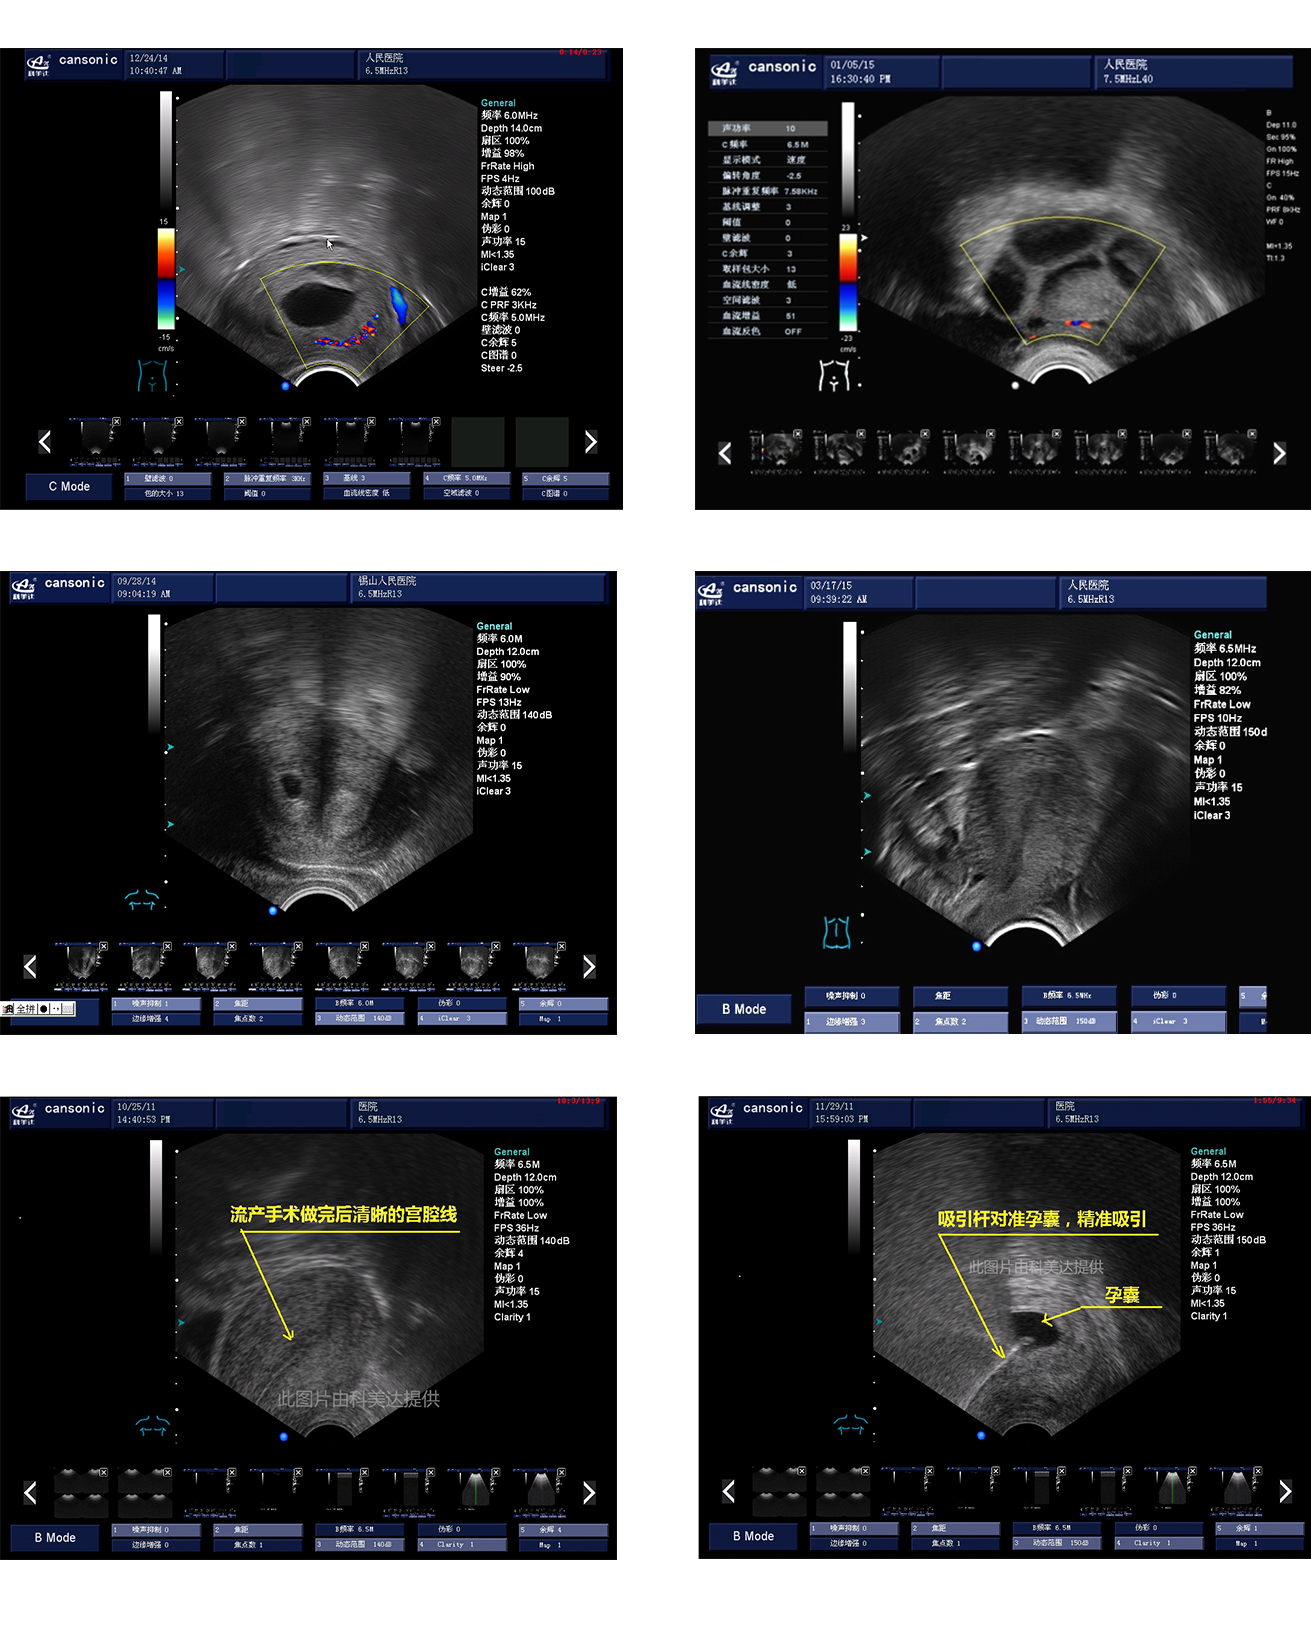

臨床圖示

1、薈萃前沿彩超技術(shù),使得超聲監(jiān)測與手術(shù)操作完美融合,實(shí)現(xiàn)宮腔手術(shù)的全程監(jiān)測

2、復(fù)合成像技術(shù),增強(qiáng)組織回聲,減少回聲失落,得到清晰、真實(shí)的手術(shù)影像

3、血流靈敏度高,清晰可見